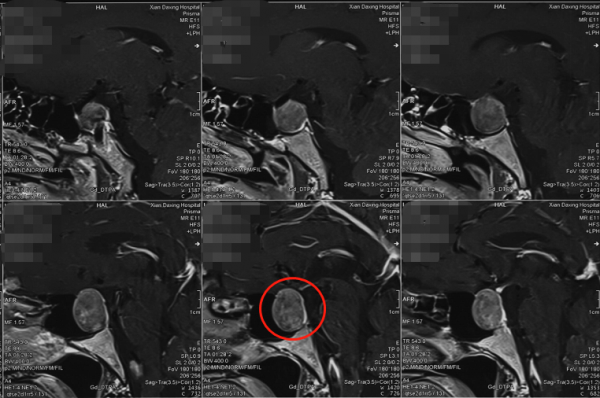

10月15日左右,賈棟教授在神經外科何幫旭醫生、麻醉科徐帥醫生協助下為劉先生實施了神經內鏡下經鼻蝶垂體瘤切除術。

術中,賈棟教授在劉先生的右鼻前庭粘膜處切開1.5釐米的小孔,從鼻腔進入,開啟鼻中隔,沿通道到達蝶鞍區的腫瘤位置, 在充分保護好海綿竇、頸內動脈、視神經等結構前提下,在錯綜複雜的神經血管狹窄間隙中,逐步分塊切除腫物,仔細刮除腫瘤,最終將腫瘤順利切除,整場手術耗時3個小時左右,手術很成功,走出手術室的那一刻,賈棟教授稍顯疲憊,但是心情卻非常高興,因為他知道劉先生很快就能恢復如初了!